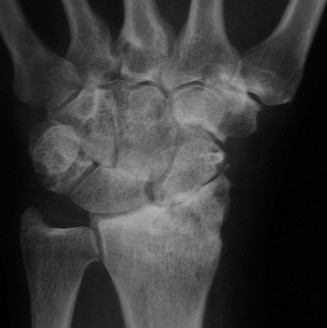

For the second patient, standard PA radiographs immediately reveal the diagnosis. We observe the classic Terry Thomas sign—a widening of the scapholunate interval greater than 3 mm. Furthermore, the lateral radiograph demonstrates a Dorsal Intercalated Segment Instability (DISI) deformity, characterized by a radiolunate angle greater than 15 degrees (lunate extended) and a scapholunate angle greater than 60 degrees.

Advanced imaging, particularly Computed Tomography (CT), is highly beneficial for preoperative templating. A fine-cut CT scan accurately maps the extent of the degenerative changes. In scapholunate advanced collapse (SLAC), arthritis follows a highly predictable, sequential pattern. It begins at the radial styloid-scaphoid articulation (Stage I), progresses to involve the entire radioscaphoid fossa (Stage II), and eventually encompasses the capitolunate joint as the capitate migrates proximally into the widened SL gap (Stage III). Notably, the radiolunate joint is universally spared in SLAC wrist due to the concentric, congruent nature of the lunate fossa and the preservation of the short radiolunate ligaments.